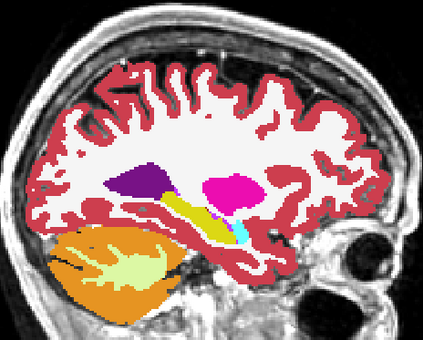

Brain atrophy and white matter hyperintensity (WMH) are critical neuroimaging features for ascertaining brain injury in cerebrovascular disease and multiple sclerosis. Automated segmentation and quantification is desirable but existing methods require high-resolution MRI with good signal-to-noise ratio (SNR). This precludes application to clinical and low-field portable MRI (pMRI) scans, thus hampering large-scale tracking of atrophy and WMH progression, especially in underserved areas where pMRI has huge potential. Here we present a method that segments white matter hyperintensity and 36 brain regions from scans of any resolution and contrast (including pMRI) without retraining. We show results on six public datasets and on a private dataset with paired high- and low-field scans (3T and 64mT), where we attain strong correlation between the WMH ($\rho$=.85) and hippocampal volumes (r=.89) estimated at both fields. Our method is publicly available as part of FreeSurfer, at: http://surfer.nmr.mgh.harvard.edu/fswiki/WMH-SynthSeg.